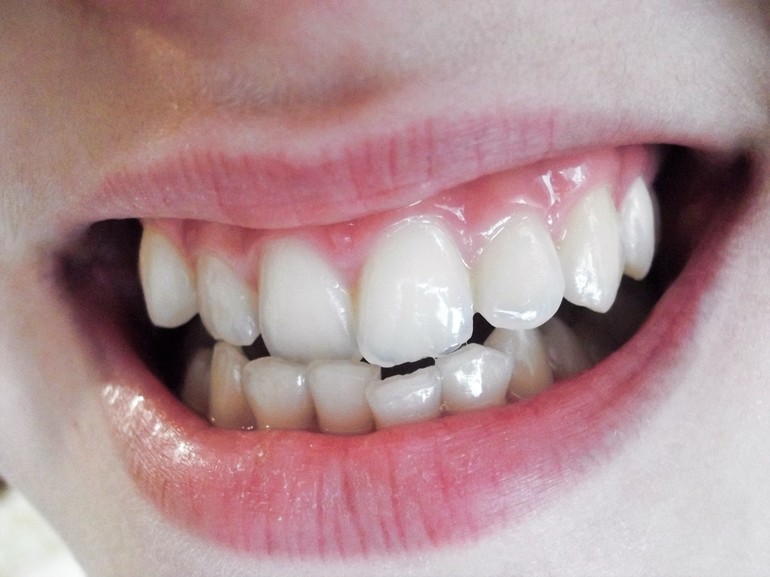

Вам пластинки еще нужны были... Скученность сильная. Еще восьмерки полезут, будет атас вообще. Вам без брекетов никак(. Копите. Ну или дочке потом придется заниматься самой, но потом сложно. Сейчас рост идет, можно расширить, чтобы все влезло.

На фото она нижнюю челюсть вперед выдвинула? Как у нее зубки смыкаются? Катя, напишите на форум, я серьезно. Там вам лучше помогут, чем здесь. Здесь нет ортодонтов. Ну или где-то в сообществе стоматология видела пост от девочки. Она ортодонт.

Катя, это серьезная проблема с прикусом. Ею надо заниматься. Это ЗУБ, орган, он должен выполнять свою функцию. Вы можете удалить его, но тогда наклонятся соседние и она их быстро потеряет. Зубы сместятся. Это не просто так - раз и все...

Я не специалист, просто сейчас прикусом занимаюсь. А что даст подпиливание? Зуб лезет под наклоном. Такое ощущение, что пятерка молочная пятерка удалена слишком рано и постоянному просто нет места. Что-то делать придется в любом случае... Удалить - это значит нанести сильный урон прикусу(.